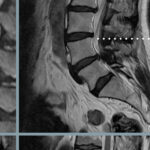

Lumbar Pathology